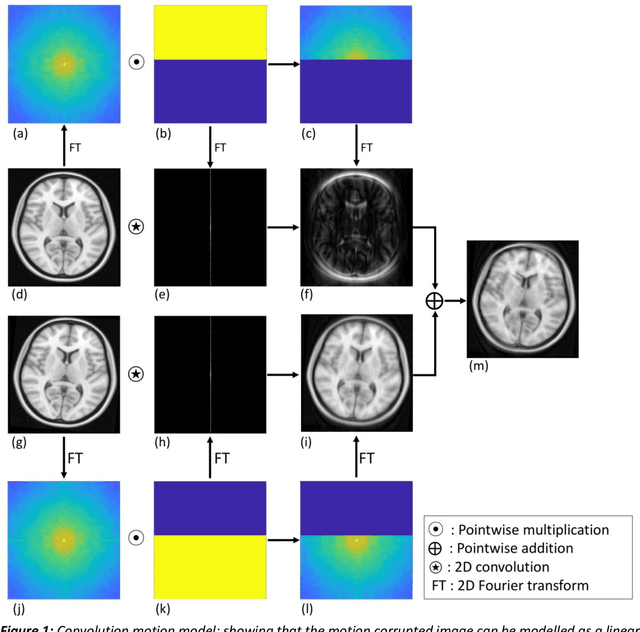

Abstract:Purpose: The suppression of motion artefacts from MR images is a challenging task. The purpose of this paper is to develop a standalone novel technique to suppress motion artefacts from MR images using a data-driven deep learning approach. Methods: A deep learning convolutional neural network (CNN) was developed to remove motion artefacts in brain MR images. A CNN was trained on simulated motion corrupted images to identify and suppress artefacts due to the motion. The network was an encoder-decoder CNN architecture where the encoder decomposed the motion corrupted images into a set of feature maps. The feature maps were then combined by the decoder network to generate a motion-corrected image. The network was tested on an unseen simulated dataset and an experimental, motion corrupted in vivo brain dataset. Results: The trained network was able to suppress the motion artefacts in the simulated motion corrupted images, and the mean percentage error in the motion corrected images was 2.69 % with a standard deviation of 0.95 %. The network was able to effectively suppress the motion artefacts from the experimental dataset, demonstrating the generalisation capability of the trained network. Conclusion: A novel and generic motion correction technique has been developed that can suppress motion artefacts from motion corrupted MR images. The proposed technique is a standalone post-processing method that does not interfere with data acquisition or reconstruction parameters, thus making it suitable for a multitude of MR sequences.